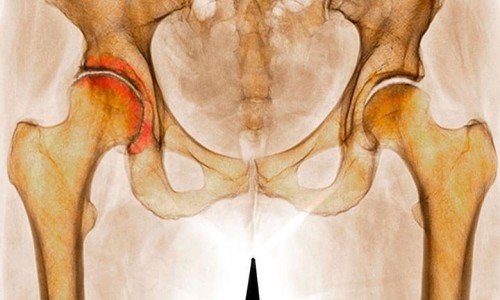

Коксартроза носи дегенеративно-дистрофичен характер, поразява предимно хора на средна и старческа възраст. Тази патология се развива постепенно, в продължение на няколко години. Съпровожда се с болки и ограничено движение в ставите. На късните стадии се наблюдава атрофия на мускулите на бедрото и скъсяване на крайниците. Може да бъде провокирана от различни фактори, сред които са: травми, вродена патология, патологични изкривявания на гръбначния стълб, възпалителни и невъзпалителни заболявания на ставата. Отбелязва се наследствена предразположеност. Понякога коксартрозата възниква без видими причини. Бива както едностранна, така и двустранна. Протича прогресиращо. На ранните стадии на коксартрозата лечението е консервативно. При разрушаване на ставите, особено при млади и пациенти на средна възраст, се препоръчва операция (ендопротезиране).

Коксартроза на тазобедрената става е дегенеративно-дистрофично заболяване на опорно-двигателната системаКоксартроза, както казахме, е дегенеративно-дистрофично заболяване. Обикновено се развива след 40-тата година. Може да е следствие от различни травми и заболявания на ставите. Понякога възниква без явна причина. Може да е както едностранна, така да е и двустранна. За коксартрозата е характерно постепенното прогресиращо протичане. На ранните стадии се използват консервативни методи за лечение. На по-късните етапи само операция може да възстанови функцията на ставата.

При коксартроза ставната течност става по-гъста и стегната. Повърхността на хрущяла изсъхва, губи се гладкостта, потрива се с неравности. Заради възникналата грапавост хрущялите при движение постоянно се травмират един друг, което предизвиква изтъняването им и влошава патологичните изменения в ставата.

При прогресиране на коксартрозата костите започват да се деформират, „приспособявайки се“ към увеличеното натоварване. Обмяната на веществата в областта на ставата се влошава. На късните стадии на коксартрозата се наблюдава мускулна атрофия на болния крайник.

На рентгенограмата на пациента, който страда от коксартроза в първа степен, се виждат леко изразени промени: умерено неравномерно свиване на ставното пространство, а също и костни разраствания около външния или вътрешния край на ацетабуларната ямка при липса на промени от страна на главата и шийката на бедрената кост.

На рентгеновите снимки се вижда значително неравномерно свиване на ставното пространство (повече от половината). Главата на бедрената кост се е изместила нагоре, деформира се и се увеличава по размер, а контурите и стават неравни. Костните разраствания при тази степен на коксартроза се появяват не само по вътрешния, но и по външния край на ацетабуларната ямка и излизат извън границите на хрущялната уста.

На рентгеновите снимки при тази степен на патологията се вижда рязко свиване на ставното пространство, изразено разширение на главата на бедрото и множество костни разраствания.